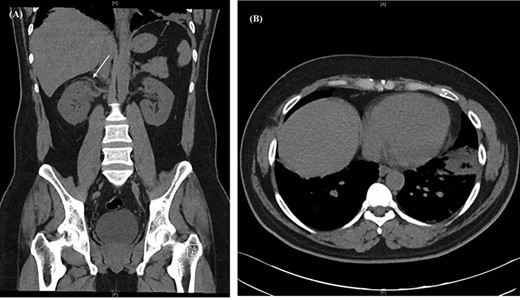

Post-discharge, he continued to experience worsening abdominal pain prompting further re-presentation. An abdominal CT with contrast showed bilateral RVT with infra-hepatic extension into the inferior vena cava (IVC) (Fig. 2). The patient was admitted under the vascular unit for a comprehensive workup.

Abdominal CT with contrast showing (A) an enlarged right renal vein with a filling defect, (B) left renal vein distension and filling defect with (C) extension into the lower intra-hepatic inferior vena cava (red arrow).